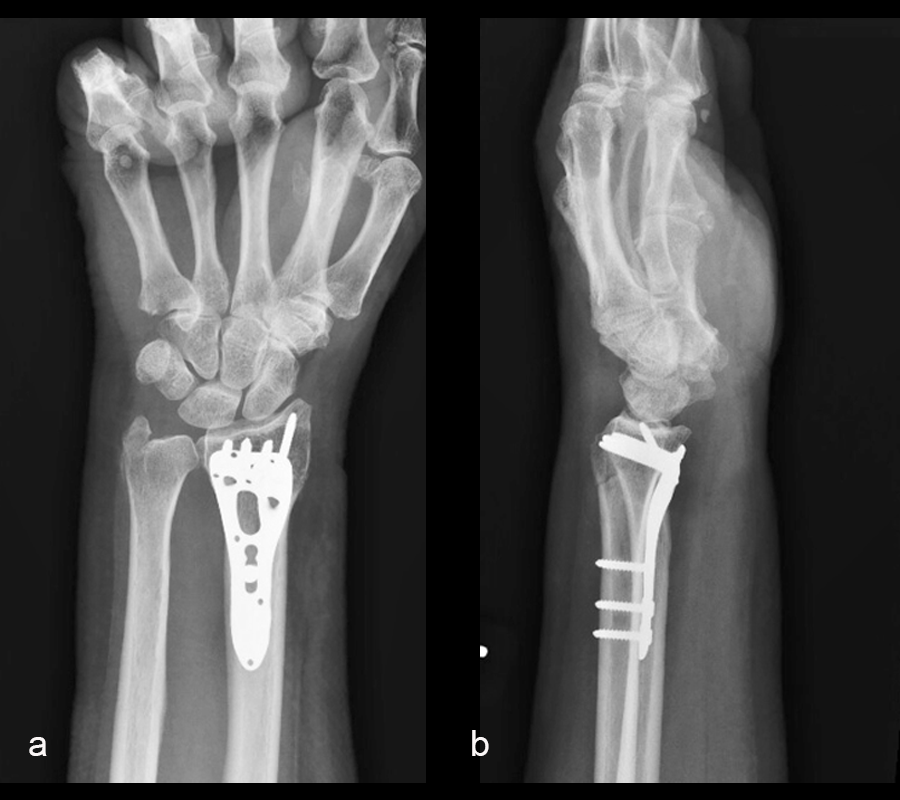

The distal radius fracture was treated with open reduction and internal fixation through a volar Henry Approach, using a VOLT™ Two-Column Distal Radius plate. At the 6-week follow-up, x-rays demonstrated a healed fracture (Fig 2). The patient’s pain had resolved and she was regaining range of motion with occupational therapy.